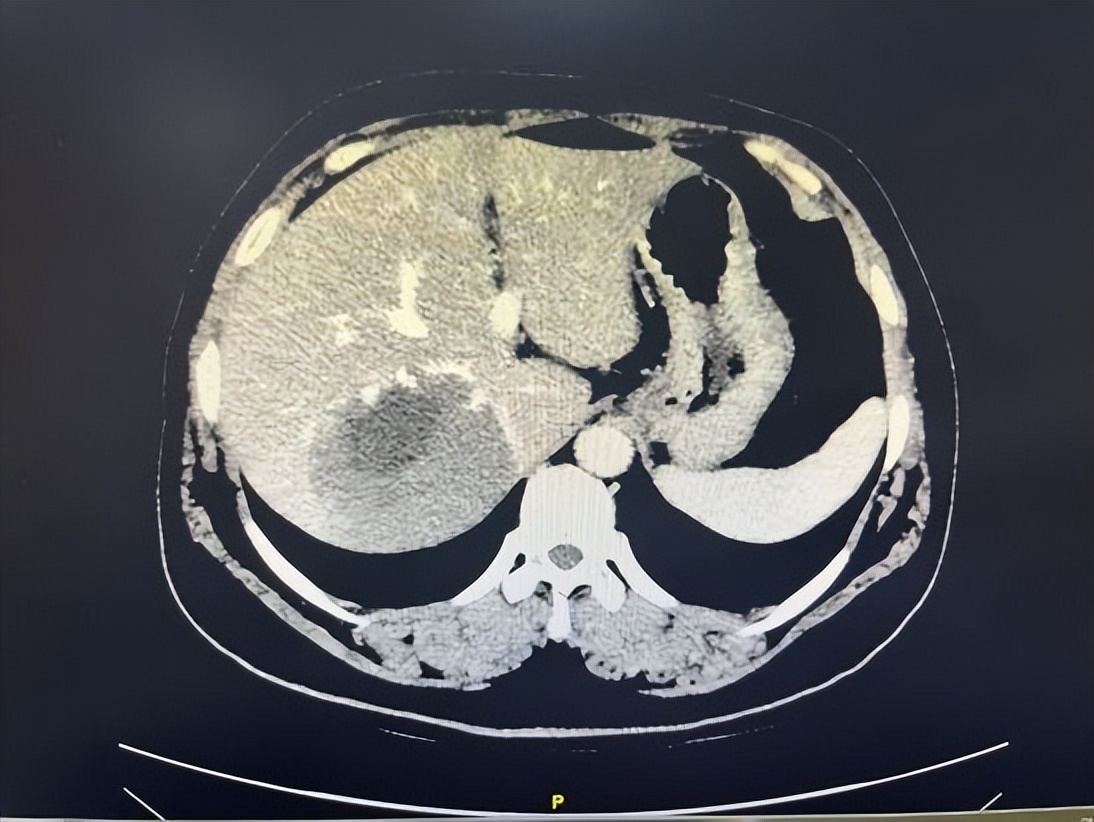

52岁的王女士一周前因腹痛并发双下肢水肿于当地医院检查发现肝脏上有一类椭圆形巨大肿瘤。在当地医生推荐下,来到哈医大一院肝脏外科就诊。入院后,陆朝阳教授团队,通过科学精密的术前检查和3D成像技术,明确肿瘤位于肝脏右后叶和尾状叶,如成年男性拳头大小,确诊为肝血管瘤,肿瘤体积巨大且位于肝脏S7段及尾状叶腔旁部并紧邻人体几条重要大血管(下腔静脉、右肝静脉、右侧门静脉),其中肿瘤后壁全程压迫整个肝后下腔静脉,右肝静脉被肿瘤头侧压扁血流流出受阻,肿瘤左侧位于肝脏尾状叶(腔旁部)曾一度被称为手术禁区,手术难度已是极大。但不仅如此,患者肝脏血管畸形,右后下肝静脉(多长一条右肝静脉)位于肿瘤足侧,将传统肝右后叶微创手术路径彻底封死,这导致想要将肿瘤安全地微创切除甚至开刀切除几乎不可能完成。

▲图1 术前肝脏CT、三维可视化提示肿瘤所在位置